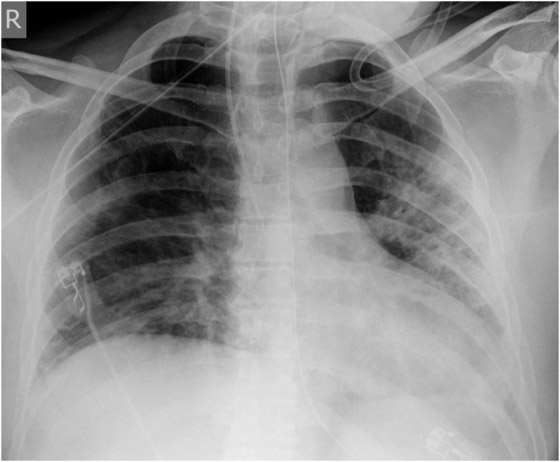

Figure 1

X-ray course of patient A. Left, normal chest x-ray (p.a., erect) at admission. Center, chest x-ray (p.a., supine) on day 4, showing massive infiltration. Right, chest x-ray (p.a., supine) day 14, after 10 days on oseltamivir and 5 days on steroids, showing regression of infiltration.

Patient A (male, 41 years), with OSAS, was hospitalised for fever and general symptoms with proven A/H1N1v infection. At that time he had leukocytosis (13 g/L), lymphopenia (11%) and a CRP count of 113 g/L, but his lung tests and chest x-ray remained normal (fig. 1a). Four days later the patient rapidly developed respiratory insufficiency requiring intubation. At this time bilateral coarse rales were heard on pulmonary auscultation and the chest x-ray showed diffuse bilateral pulmonary infiltrates (fig. 1b). Oseltamivir was started only then. The disease course was highly complicated with the longest duration of hospitalisation in this series (36 days, including 19 days in intensive care, 13 days intubated). Figure 1c shows slow recovery on day 14 after 10 days of oseltamivir and 5 days of steroids. Recovery was further complicated by generalised weakness requiring admission to a rehabilitation unit.